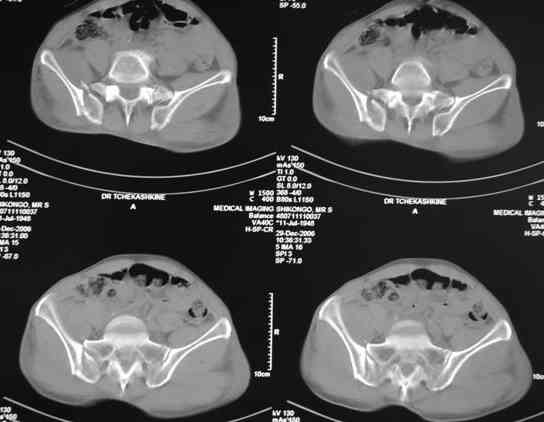

По-поводу фиксации таза спонгиозными винтами. Данный способ все-таки показан для фиксации повреждения крестцово-подвздошного сочленения или переломов крестца. Мне кажется, что в данной случае ситуация иная - имеется перелом "основания" крыла подвздошной кости (в который вовлечена и поверхность, составляющая крестцово-подвздошное сочленение). Не уверен, что фиксация данного повреждения (и заднего полукольца) винтами будет стабильной, так как именно на уровне 1-2 крестцовых позвонков (где обычно вводят винты) линия перелома уходит в латеральном направлении от крестцово-подвздошного сочленения.

PI>По-поводу фиксации таза спонгиозными винтами. Данный способ все-таки показан

для фиксации повреждения крестцово-подвздошного сочленения или переломов крестца. Мне кажется, что в данной случае ситуация иная - имеется перелом

"основания" крыла подвздошной кости (в который вовлечена и поверхность, составляющая крестцово-подвздошное сочленение). Не уверен, что фиксация данного повреждения (и заднего полукольца) винтами будет стабильной, так как

именно на уровне 1-2 крестцовых позвонков (где обычно вводят винты) линия перелома уходит в

латеральном направлении от крестцово-подвздошного сочленения.

Я просмотрел томограммы и у меня создалось впечатление, что винтам есть за что *зацепиться*. В сочетании с 5 мм Шанц винтами, проведенными через нижне-переднюю ость спереди назад через КП сочленения -стабильность тазового кольца должна восстановиться. - Это , конечно, при условии , что закрытая рнепозиция будет успешной.

после КТ отказался от этой идеи - двусторонний перелом крестца в зоне 1 - алярная часть, при попытке низведения правого гемипелвиса теоретически есть вероятность смещения

фрагмента крестца слева.